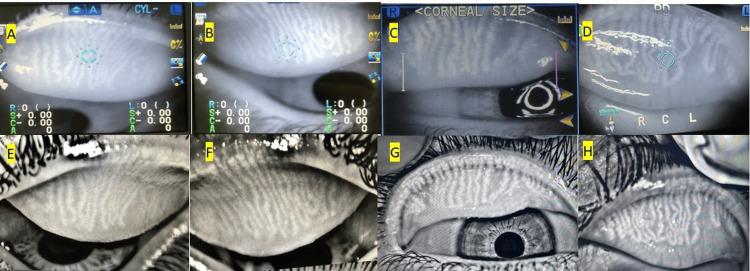

Introduction This study proposes the utility of an infrared auto refractometer for meibography and compares miebographs obtained by an auto refractometer to meibographs obtained by a designated meibography machine. Methods A prospective observational comparative study of meibographs of patients with clinical signs of meibomian gland dysfunction (MGD) using a designated meibography machine and an infrared auto refractometer. Five masked, experienced interpreters graded the images of the two machines. The Kappa test was used to calculate Intra-rater and inter-rater agreements between the meibography machine and automated refractor grading of meibomian gland dysfunction. Results High-quality photos of all 30 eyes delineating the meibomian glands (MG) were successfully obtained with both the meibography machine and the autorefractor. Both methods had a good intra-rater agreement (κ= 0.667 to 0.784, average 0.738). Poor to fair interrater agreement was noticed in the grading of autorefractor images (k= -0.030 to 0.343, average 0.092) and poor to moderate agreements between investigators for meibography machine images (K= -0.016 to 0.420, average 0.173). Conclusion A commercially available auto refractometer could capture high-quality non-contact IR digital meibographs.

引言 本研究提出了一种红外自动验光仪用于睑板腺造影的效用,并将自动验光仪获得的睑板腺造影与指定睑板腺造影机获得的睑板腺造影进行比较。方法 采用指定睑板腺造影机和红外自动验光仪对有睑板腺功能障碍(MGD)临床体征的患者进行睑板腺造影的前瞻性观察比较研究。五名经验丰富的蒙面口译员对两台机器的图像进行评分。使用Kappa检验计算睑板腺造影机与自动验光仪对睑板腺功能障碍分级之间的评分者内和评分者间一致性。结果 使用睑板腺造影机和自动验光仪均成功获得了所有30只眼睛描绘睑板腺(MG)的高质量照片。两种方法均具有良好的评分者内一致性(κ = 0.667至0.784,平均0.738)。在自动验光仪图像分级中观察到评分者间一致性较差至中等(k = -0.030至0.343,平均0.092),在睑板腺造影机图像方面,研究者之间的一致性较差至中等(K = -0.016至0.420,平均0.173)。结论 市售的自动验光仪可以捕获高质量的非接触式红外数字睑板腺造影照片。